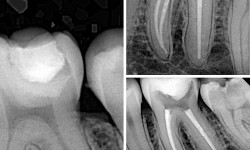

Якщо карієс прогресував до пульпи зуба то починає боліти зуб на різні чинники наприклад на: холодне, горяче, біль в ночі.

В такому випадку потоібно лікувати кореневі канали.